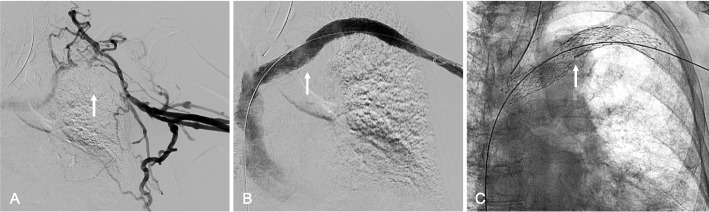

Methods: Thirty-eight patients (43 affected limbs) with symptomatic ASVT and no prior treatment or surgical decompression underwent endovascular placement of dedicated venous stents across the thoracic outlet with Abre Venous Stents (Medtronic, Dublin, Ireland), Venovo Venous Stents (BD, Franklin Lakes, NJ, USA), or Vici Venous Stents (Boston Scientific, Marlborough, MA, USA). Stents were extended peripherally to the subclavian or axillary veins and centrally to the brachiocephalic vein or SVC. Technical success was defined as successful stent deployment across the costoclavicular space, and clinical success as symptomatic improvement.

Results: Stent placement was technically successful in all 43 limbs (100%), with clinical improvement observed in 97.4% of patients. The one patient without clinical improvement experienced early thrombosis of the stent, requiring mechanical thrombectomy and additional stenting. Follow-up CT venography at a mean of 301.3 days demonstrated high primary stent patency rates (81.4%), with stent crushing observed in only 7.0% of limbs and no instances of stent fracture. Adverse events were limited, including two access site hematomas and one hypotensive episode, all of which resolved without evidence of long-term complications.